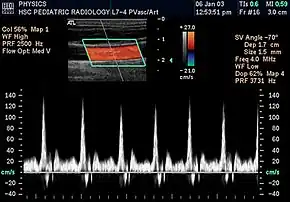

![]() Spectral duplex scan of the common carotid artery | |

Duplex ultrasonography sometimes refers to Doppler ultrasonography or spectral Doppler ultrasonography.[3] Doppler ultrasonography consists of two components: brightness mode (B-mode) showing anatomy of the organs, and Doppler mode (showing blood flow) superimposed on the B-mode. Meanwhile, spectral Doppler ultrasonography consists of three components: B-mode, Doppler mode, and spectral waveform displayed at the lower half of the image. Therefore, "duplex ultrasonography" is a misnomer for spectral Doppler ultrasonography, and more exact name should be "triplex ultrasonography".[3]

Colour Doppler shows the direction of the blood flow in red or blue (either towards or away from the transducer). Meanwhile, spectral Doppler not only shows the direction of blood flow, it also shows the phases (pulsatility) and acceleration of the blood flow. Any sudden changes in direction of blood flow produces audible sounds on the ultrasound machine.[3]

In spectral Doppler, the y-axis shows the direction and velocity of the flow. Meanwhile, the x-axis (as known as "baseline") shows the flow over time. The gradient at any point on the waveform would therefore shows the acceleration of the flow. In "antegrade" flow, the blood flows according to the normal flow within the circulatory system (e.g. veins flow towards the heart while arteries flows away from the heart). In "retrograde" flow, the flow would reverse (e.g. veins flow away from heart or arteries flow towards the heart). However, "retrograde" flow can be both abnormal or normal. For example, in portal hypertension, there is an abnormal portal venous flow where it flows away from the liver (hepatofugal flow) instead of the normal flow towards liver (hepatopetal flow). In jugular venous pressure waveform of the internal jugular vein, the retrograde "a" waveform is a normal flow due to right atrium contraction. Both antegrade or retrograde flow can be either towards or away from the probe transducer, depending on the position of the probe relative to the blood flow. Blood flow toward the transducer would appear above the baseline while blood flows away from the transducer will appear below the baseline. Waveform of the flow can be classified as: pulsatile (as in arteries), phasic (as in veins), non-phasic (as in diseased veins), and aphasic (no flow). Spectral broadening (thickness of the waveform) increases from large vessels (plug flow) to medium vessels (laminar flow) to small/stenotic/diseased vessels (turbulent flow) due to a larger variety of blood with different ranges of velocities in those with turbulent flow.[3]